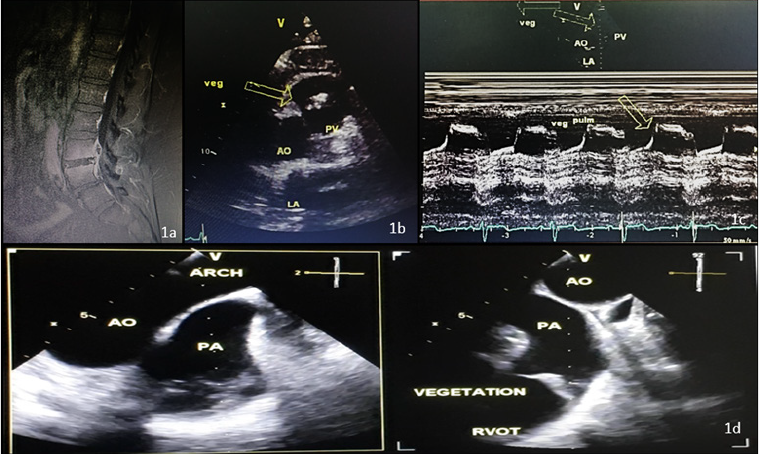

A 61 year old male patient presented to his primary physician for back pain for more than 3 months. His history revealed no previous medical issues, but the patient mentioned an episode of community acquired pneumonia 4 months before his presentation to the clinic. He noticed the need for intravenous antibiotics for 2 weeks. In addition, patient still complaining from a nonproductive cough since his treatment. He had no fever nor night sweats but complained of fatigue and arthralgia. On physical examination, lungs were clear, no pitting edema, normal heart sounds although a murmur was heard on the left lateral sternal border. Patient report pain on percussion over the spinal segment but no or little pain on pressure. Inclining and straightening up again causes pain to increase. Pain on knee flexion was also seen. Upon exertion pain also increases. Laboratory tests revealed normal blood count with normal white blood cells and normal inflammatory parameters (CRP, ESR, Procalcitonin.). Blood cultures were negative. MRI of the spine showed erosions of the vertebral plates in L4 and L5 with epidural thickening pushing back the dural sac with peripheral enhancement and hypointense center of the intervertebral disc of L4 and L5 in favor of an epidural abscess.Furthermore, an edematous regional infiltration of the psoas muscle are common signs of spondylodiscitis with an anterior epidural abscess (Figure 1A).

Figure 1A: MRI of the spine revealing an epidural abscess with signs of spondylodiscitis.

Figure 1B: Transthoracic echocardiography (short axis) revealing a hyperechogenic image on the pulmonary valve

measuring(14x20mm) suspicious of a vegetation.

Figure 1C: Transthoracic echocardiography, signs of vegetation on TM .

Figure 1D: Transesophageal echocardiography with a view of the pulmonary valve and signs of vegetation with a moderate

pulmonary regurgitation.

Cardiac ultrasound revealed a preserved Left ventricular function with no indirect signs of pulmonary hypertension, normal diastolic function and left ventricular end diastolic pressure with an aneurysmal interatrial septum. Aortic and mitral valve were normal but there was a moderate pulmonary regurgitation grade II with a hyperechogenic image on the pulmonary valve measuring(14x20mm) suspicious of a vegetation. (Figure 1B & 1C)TEE showed signs of a pulmonary vegetation with a moderate pulmonary regurgitation and no signs of abscess [Figure1d]. Treatment with antibiotics for 6 weeks was initiated. Cardiac ultrasound after regimen revealed stable vegetation more hyperechogenic and calcified as a sign of chronic endocarditis. His last MRI revealed complete regression of the epidural collection with residual signs of spondylodiscitis. Patient stable, pain is better and follow up with cardiac ultrasound every 6 months is mandatory. No signs of right ventricular dysfunction were noticed and pulmonary regurgitation still stable. Patient feeling better.